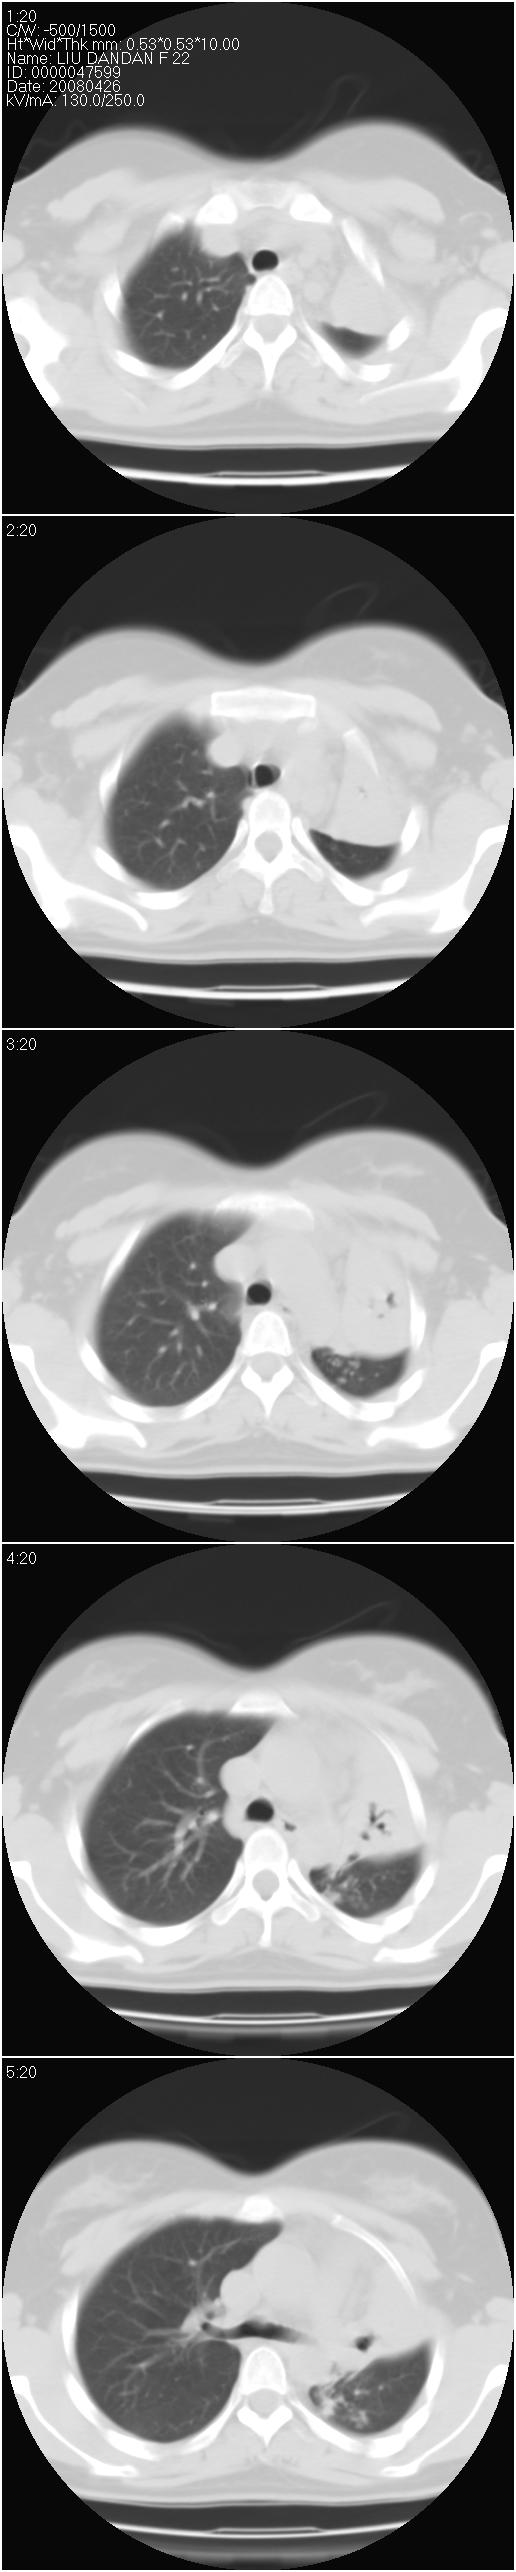

以下是引用光影相伴在2008-4-26 11:32:00的发言:[br]左肺继发性结核伴左肺上叶肺不张。建议:行纤维支气管镜检查排除支气管内膜结核。

以下是引用光影相伴在2008-4-26 11:32:00的发言:[br]左肺继发性结核伴左肺上叶肺不张。建议:行纤维支气管镜检查排除支气管内膜结核。

以下是引用zsl6918在2008-4-26 16:18:00的发言:[br]符合支气管内膜结核的诊断。

以下是引用光影相伴在2008-4-26 11:32:00的发言:[br]左肺继发性结核伴左肺上叶肺不张。建议:行纤维支气管镜检查排除支气管内膜结核。

以下是引用有风的日子在2008-4-26 13:54:00的发言:[br][quote]以下是引用光影相伴在2008-4-26 11:32:00的发言:[br]左肺继发性结核伴左肺上叶肺不张。建议:行纤维支气管镜检查排除支气管内膜结核。